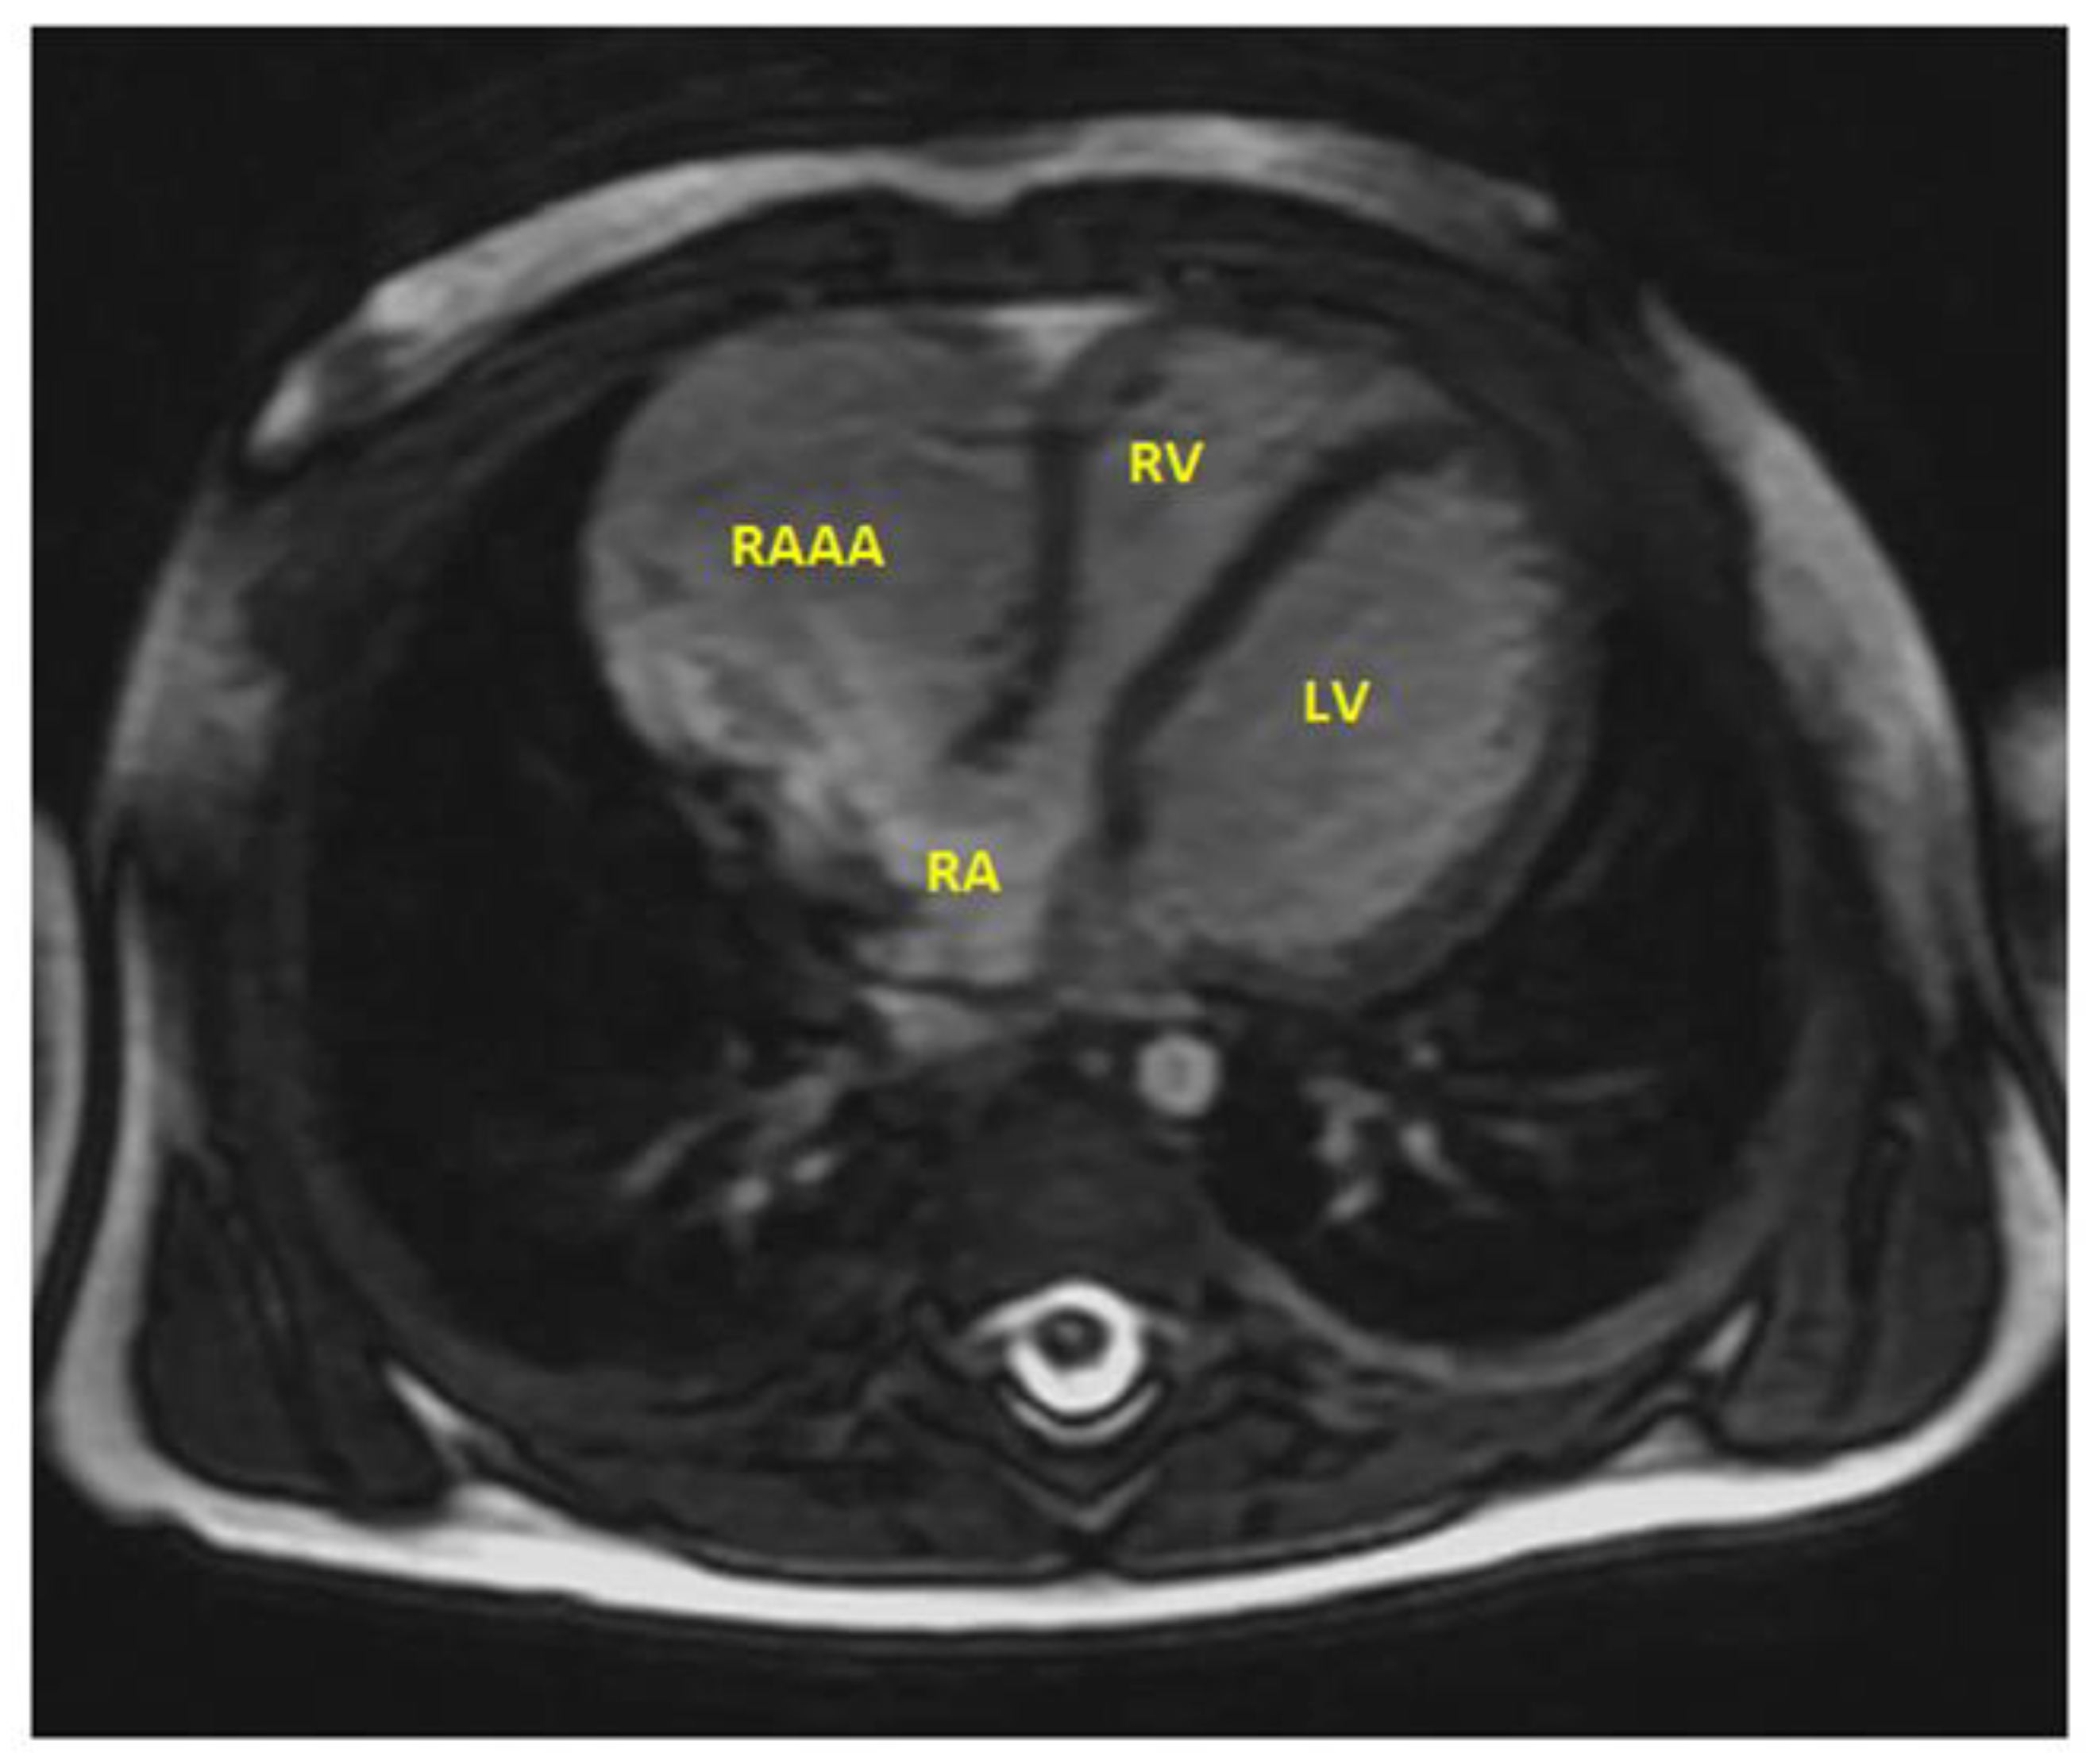

- MRI provides useful information regarding the cardiac structure, the thickness of the wall, and the route of the right coronary artery, as well as potential sites of compression.

| MRI | Magnetic Resonance Imaging |